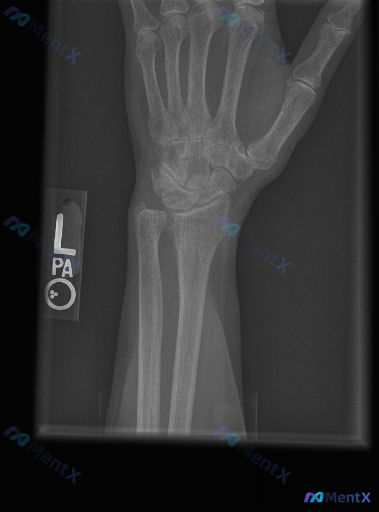

大家好,今天遇到一份左手腕关节正位(PA)X光片。影像分析显示:桡骨远端、尺骨远端及所有腕骨骨皮质连续,未见明确骨折线;桡腕关节、下尺桡关节及腕中关节对位良好,间隙正常;骨质密度均匀,无溶骨性破坏或占位;腕周软组织清晰,无肿胀或异物。 但临床背景需要注意:如果患者有明确的外伤史,或者持续腕部疼痛、功...